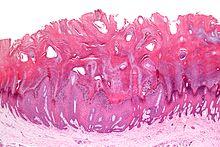

Common warts have a characteristic appearance under the microscope. They have thickening of the stratum corneum (hyperkeratosis), thickening of the stratum spinosum (acanthosis), thickening of the stratum granulosum, rete ridge elongation, and large blood vessels at the dermoepidermal junction.

Micrograph (H&E stain) of a common wart (verruca vulgaris) showing the characteristic features (hyperkeratosis, acanthosis, hypergranulosis, rete ridge elongation, and large blood vessels at the dermoepidermal junction)